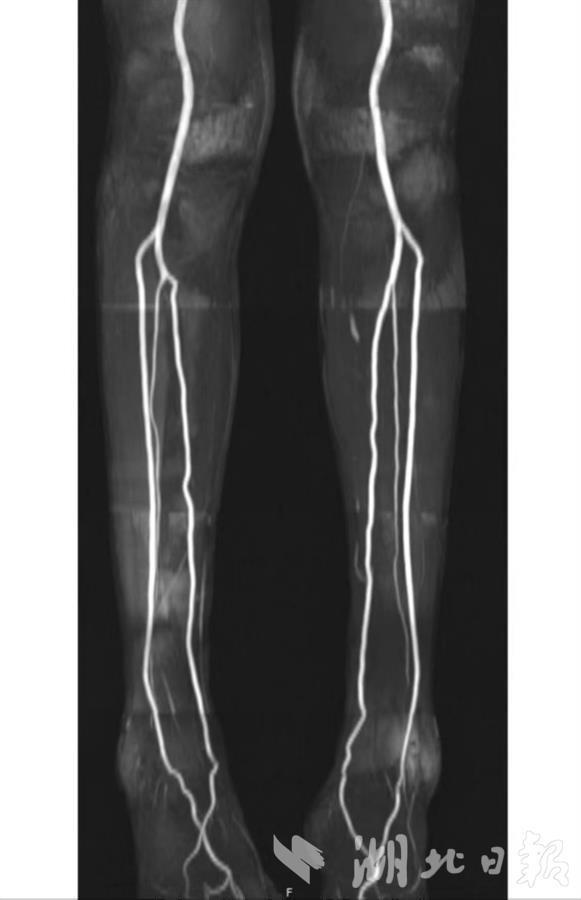

为此,吴刚团队多年来专注于磁共振新技术新序列的开发与改良。经过多年努力,他们研发出一种无需电离辐射、无需造影剂、可在短时间内反复多次扫描的磁共振动脉造影(MRA)技术,解决了全身血管诊断难题。目前,此技术已经成熟应用于临床。

吴刚介绍,新技术不仅能获得患者胸部大动脉的优质影像,也能清晰显示双足、双手小动脉影像,还能用于显示肾功能不全患者的肾动脉、糖尿病血管病、动脉粥样硬化等。其动脉成像图像质量高,零射线,零造影剂,对身体危害小。他提醒,一旦发现皮肤红斑、口干、眼干等症状要警惕血管炎,需及时到正规医院找专科医生进行检查,以免延误治疗。